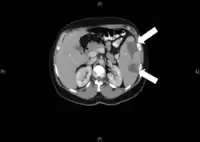

При генералізованому перебігу ЦМВ-інфекції метаморфозу піддаються клітини епітелію практично всіх органів і систем. В результаті розвивається вогнищева або інтерстиціальна пневмонія, підгострий холестатичний гепатит, вогнищевий нефрит, катаральний або виразковий ентероколіт. Можливе формування вад розвитку кишечника та інших внутрішніх органів. При ураженні головного мозку розвиваються вогнищеві некрози і кальцифікати. Періодично відбувається реактивація інфекційного процесу. Як правило, це зумовлено зниженням кіллерної функції лімфоцитів і/або продукції інтерферону. При різкому пригніченні активності природних кілерів можливе швидке поширення вірусів через кров та лімфою у різні органи і тканини, генералізація інфекції та навіть розвиток септичних станів. Крім того, взаємне поєднання інфекцій, пов'язаних з ураженням вірусом CD4-клітин (ЦМВ-інфекція, ВІЛ-інфекція, туберкульоз), призводить до ускладнення перебігу кожної з них і поглиблення імуносупресії.

В імуноскомпрометованих осіб ЦМВ-інфекція завжди має генералізований характер і може уражати різні органи і системи з розвитком тяжкої пневмонії, міокардиту, енцефаліту, асептичного менінгіту, тромбоцитопенії, гемолітичної анемії, гастриту, гепатиту, ретиніту (запалення сітківки ока) тощо. Нерідко розвивається дисемінована форма ЦМВ. Найбільш частим проявом ЦМВ-інфекції при ВІЛ-інфекції є ретиніт, рідше — езофагіт, коліт, полірадикулопатія (порушення функції спинномозкових нервів), енцефаліт.